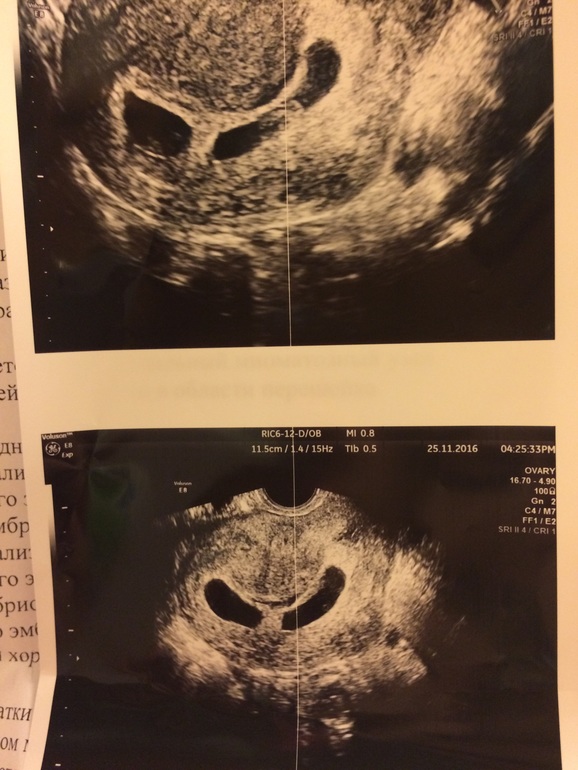

23 дпп пятидневок

23 дпп пятидневок 119 фотографий